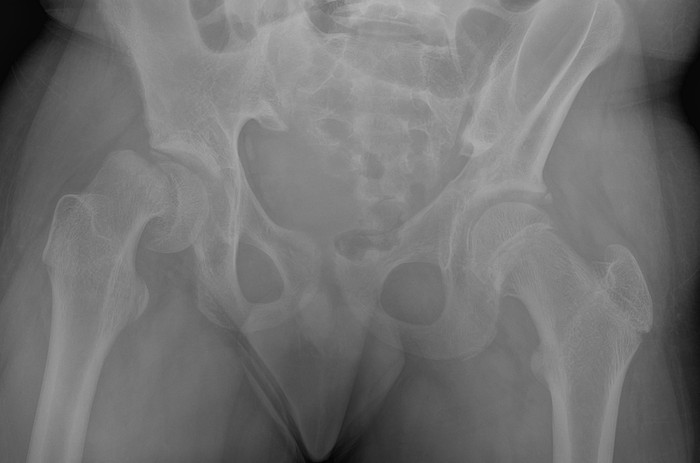

환자의 나이, 아파한 내력, 신체 검사, 동반된 질환 등을 종합해보면 어느 정도 짐작할 수 있고, 단순 방사선 검사로 확진할 수 있다. 그러나 초기에 엉덩이 관절을 측면에서 촬영하지 못하면 발견하지 못하는 수도 있다. 확진은 단순 방사선 검사로 한다. 아주 초기에 질병이 의심되나 방사선 검사에서 확인되지 않으면 MRI 검사가 도움이 될 수도 있다. 병이 심해서 뼈 수술이 필요한 경우에는 수술 계획을 세우기 위해 컴퓨터 촬영이 필요할 수도 있다.